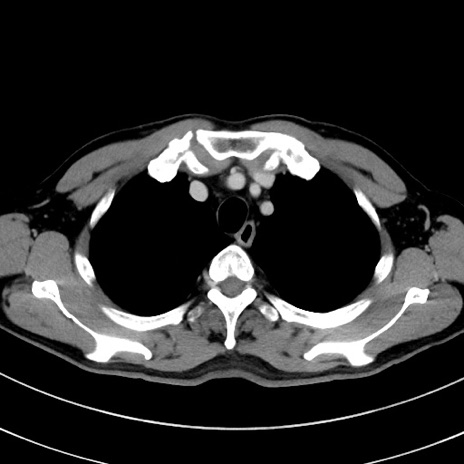

症例8(横断像)

【症例】 60歳代男性

【主訴】 黒色吐物

【現病歴】 4日前から嘔気自覚、2日前の朝食後にも嘔気あり、自分で手で嘔吐反射起こし嘔吐したところ血が混ざっていたため受診。

【既往歴】 5年前汎発性腹膜炎を伴う急性虫垂炎で手術、高血圧、前立腺肥大症、高脂血症

【身体所見】 腹部正中に手術癩痕あり 腹部平坦・軟圧痛なし膨満感あり

【データ】WBC 8400、CRP 4.54